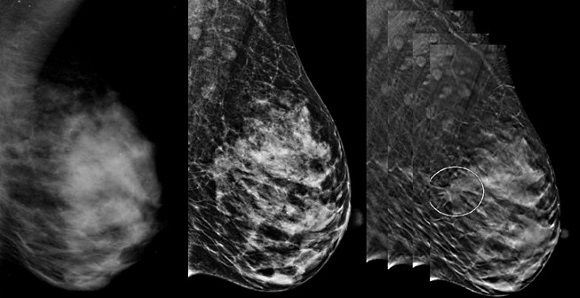

Томосинтез молочных желез: что это и как проводится исследование